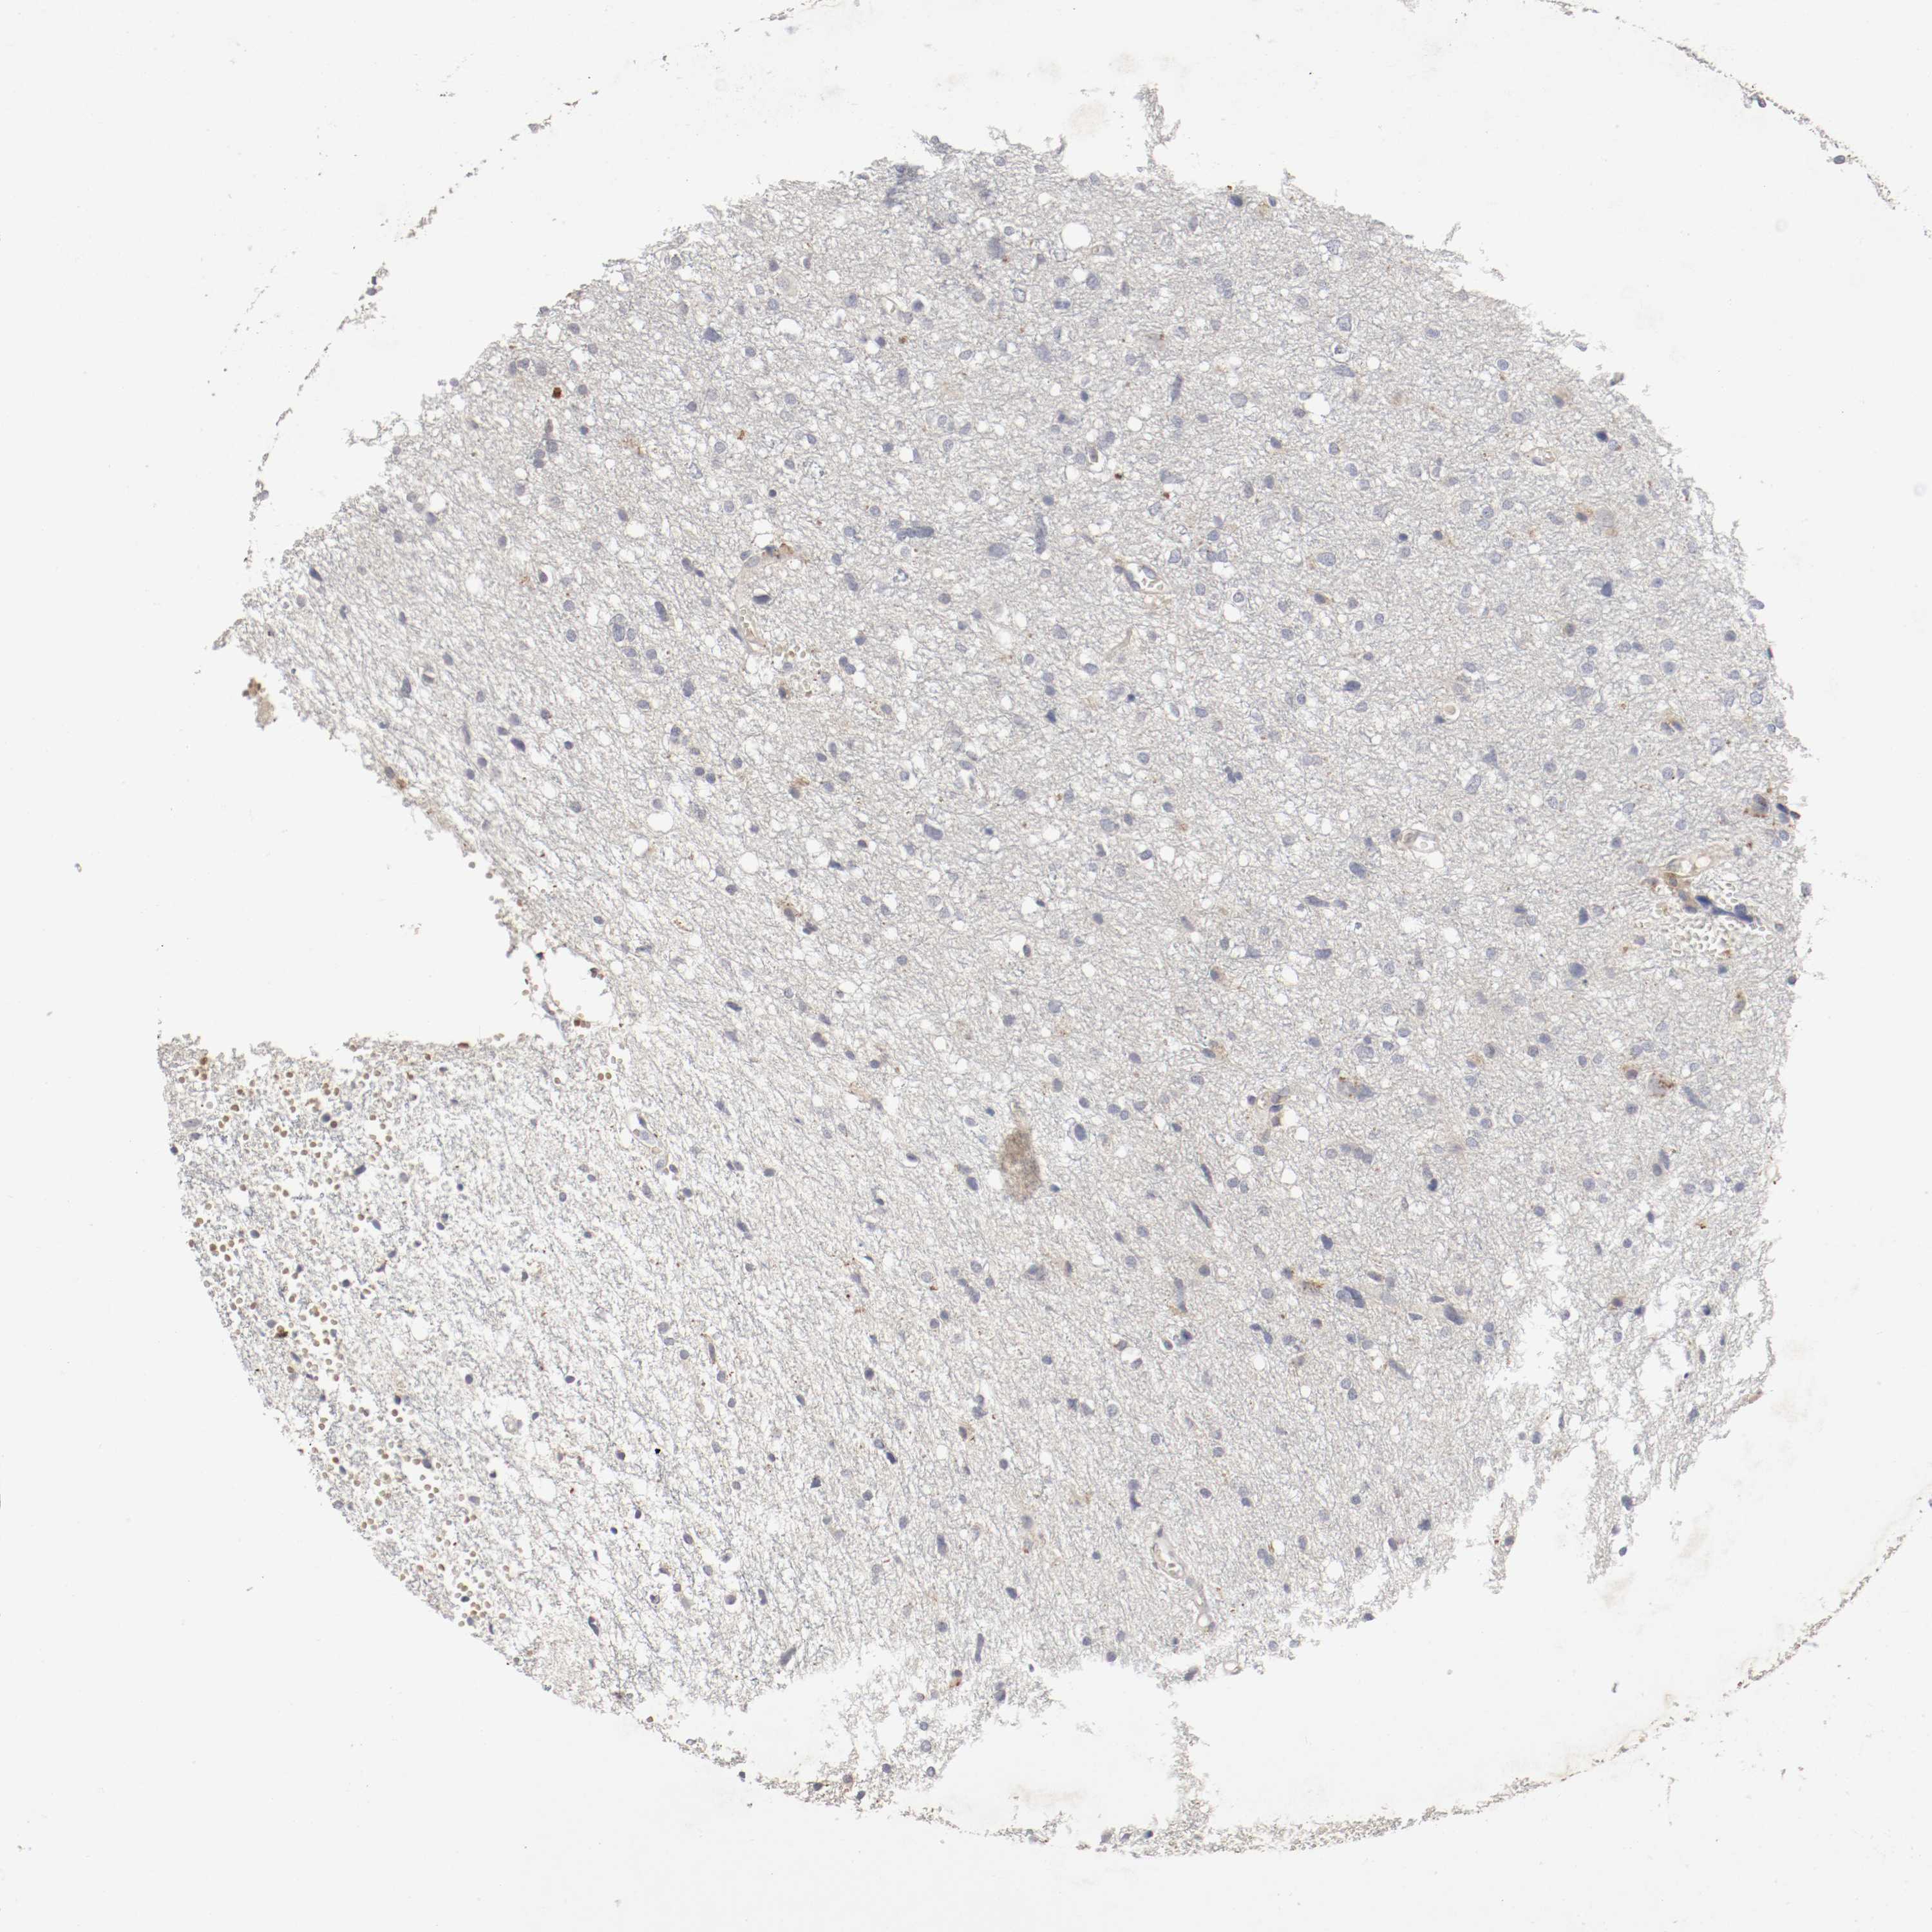

GLIOMA - Protein expressioni

A mouse-over function shows sample information and annotation data. Click on an image to view it in a full screen mode. Samples can be filtered based on level of antibody staining by selecting one or several of the following categories: high, medium, low and not detected. The assay and annotation is described here.

Antibody stainingi

Antibody staining in the annotated cell types in the current human tissue is reported as not detected, low, medium, or high, based on conventional immunohistochemistry profiling in selected tissues. This score is based on the combination of the staining intensity and fraction of stained cells.

Each image is clickable and will lead to virtual microscopy that enables deeper exploration of all samples and also displays staining intensity scores, fraction scores and subcellular localization as well as patient and tissue information for each sample.

Antibody HPA005131

Staining

High

Medium

Low

Not detected

Intensity

Strong

Moderate

Weak

Negative

Quantity

>75%

75%-25%

<25%

None

Location

Nuclear

Cytoplasmic/membranous

Cytoplasmic/membranous,nuclear

Glioma, malignant, High grade

Glioma, malignant, NOS

Glioma, malignant, Low grade